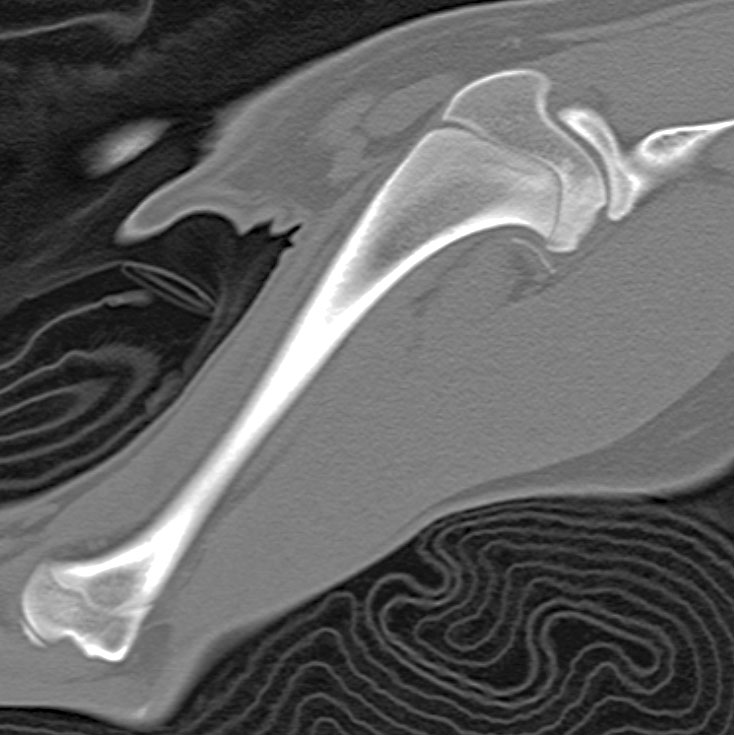

A six-month-old intact female border collie presents with left forelimb lameness. A CT scan of the left shoulder is provided.

A CT scan of a dog's left shoulder.

Photo courtesy Dr. Kendra Freeman